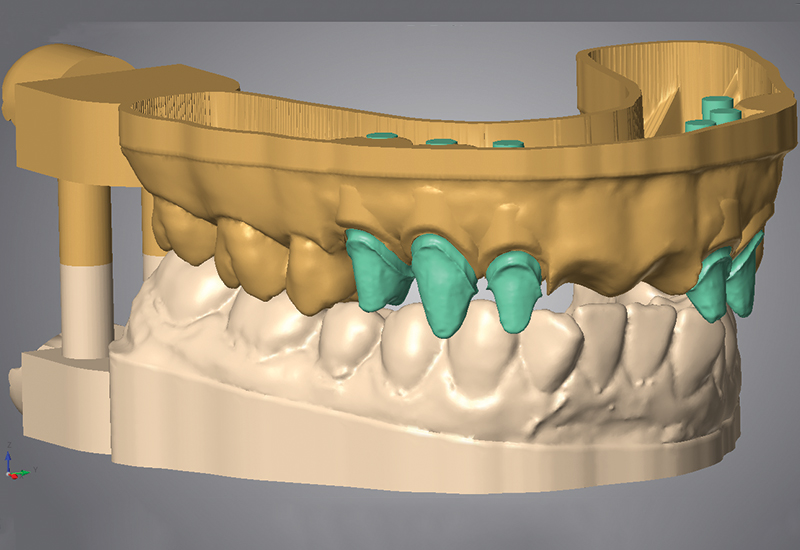

اکنون متخصصان بخش دندانپزشکی می توانند اسکن سه بعدی دهان و طراحی فایل سه بعدی CAD را، خود انجام دهند. سپس می توانند با پرینتر سه بعدی رومیزی خود و یا با خدمات پرینت سه بعدی آنلاین، پرینت سه بعدی خود را تولید کنند. کسب و کارهای دندانپزشکی در حال پیشرفت هستند واستفاده از فناوری های جدید مانند پرینترهای سه بعدی و اسکنرهای سه بعدی اختصاص یافته به کار دندانپزشکی توسعه یافته است. آزمایشگاه های دندانپزشکی بیشتر و بیشتر از این تکنولوژی برای توسعه روش های جدید کار استفاده می کنند و بسیاری از پرینترهای سه بعدی برای ترمیم سریع دندان ها، دستگاه های ارتودنسی یا ایمپلنت های سه بعدی چاپی و تاج های دندانی ایجاد می کنند.

پرینت سه بعدی راه حلی تکاملی برای ساخت اقلام سفارشی برای همه بخش ها است اما در بخش پزشکی نمود بیشتری پیدا کرده است. در زمینه مراقبت های بهداشتی، برخی از راه حل ها باید با بیماران تطبیق داده شود. به طور معمول، پروتز یا ایمپلنت باید با ساختار بیمار مطابقت داشته باشد. و این موضوع مخصوصا برای دندانپزشکی صادق است، زیرا همه ساختار دندانهای منحصر بفرد خود را دارند و دهان بیماران با هم متفاوت است. در حال حاضر می توان یک مدل دقیق از دندان بیمار تهیه کرد که با راه حل هایی که با بیمار کاملا سازگار است منجر به ترمیم سه بعدی دندان ها می شود.

با توجه به موجود بودن اسکنرهای دندانپزشکی در بازار، اسکن سه بعدی کردن دندان بیمار آسان است. اسکن های پزشکی معمولا به فرمت DICOM می باشند که توسط نرم افزارهای مدل سازی معمول پشتیبانی نمی شود. شما می توانید از نرم افزار OsiriX استفاده کنید که شما را قادر می سازد تا فایل خود را به صورت دو بعدی یا سه بعدی پردازش کنید. به این ترتیب شما می توانید از دو نرم افزار برای کارآیی مفید تصویربرداری کامپیوتری استفاده کنید. تعداد زیادی نرم افزارهای مدل سازی سه بعدی مختص صنعت پزشکی در دسترس می باشد. این نرم افزار سه بعدی می تواند به شما تجسم سه بعدی از مدل مورد نظر بدهد. استفاده از یک نمایشگر سه بعدی به این امر کمک می کند. نرم افزار مدل سازی سه بعدی می تواند به شما کمک کند که مدل سه بعدی را به دلخواه تغییر داده و با نیاز خود تطبیق دهید. توانایی مدل سازی دندان ها با استفاده از این ابزارها بی پایان است.

- ۳shape، که به طور خاص برای مدل سازی سه بعدی دندانپزشکی ساخته شده است. بسته های مختلف براساس نیازهای شما در دسترس هستند. شما می توانید یک نسخه برای تاج دندان و پل، یکی برای اسکنها، و یا بسته هایی با تمام گزینه های مختلف تهیه کنید.